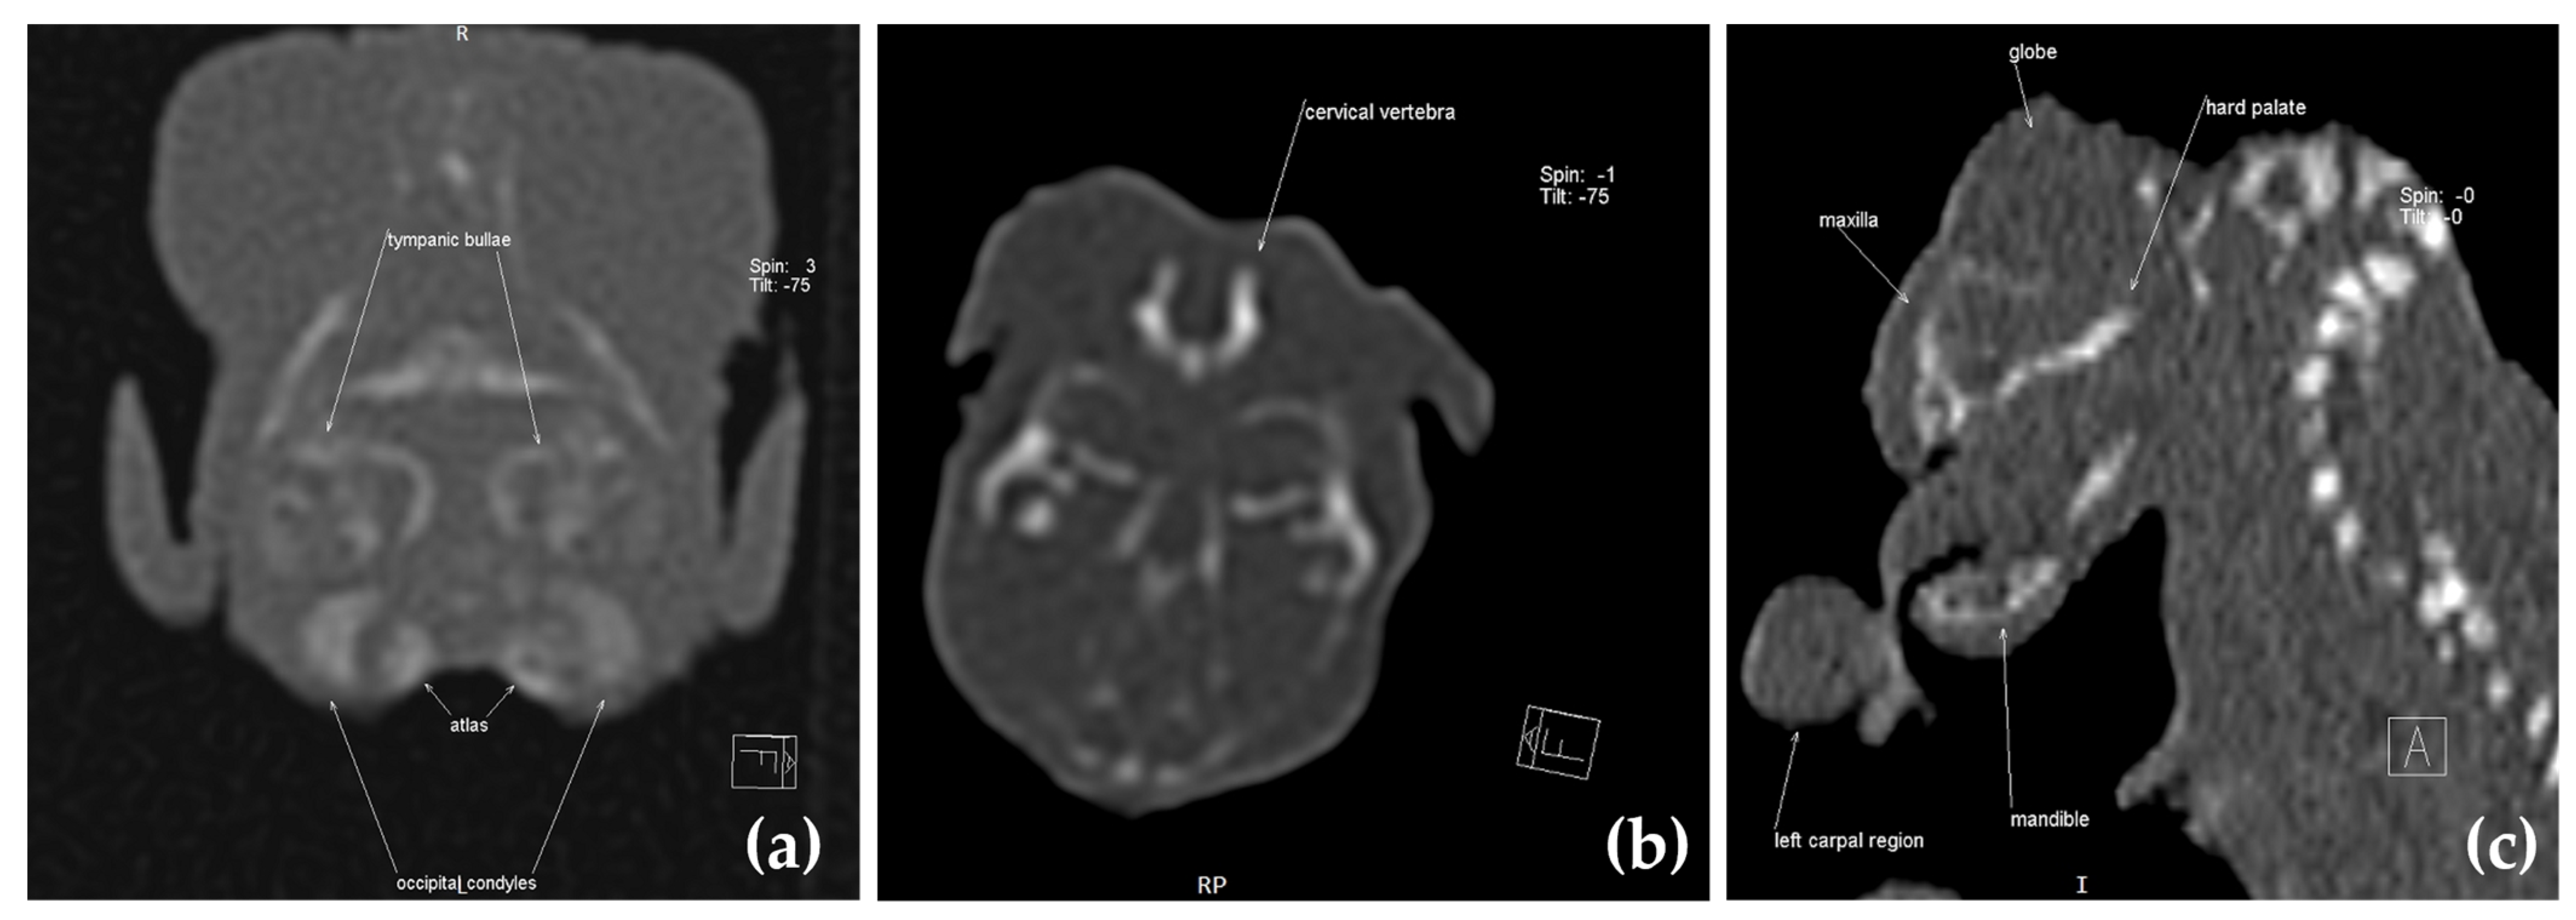

2.3. Computed Tomography Investigation

3. Results

3.1. Clinical Presentation